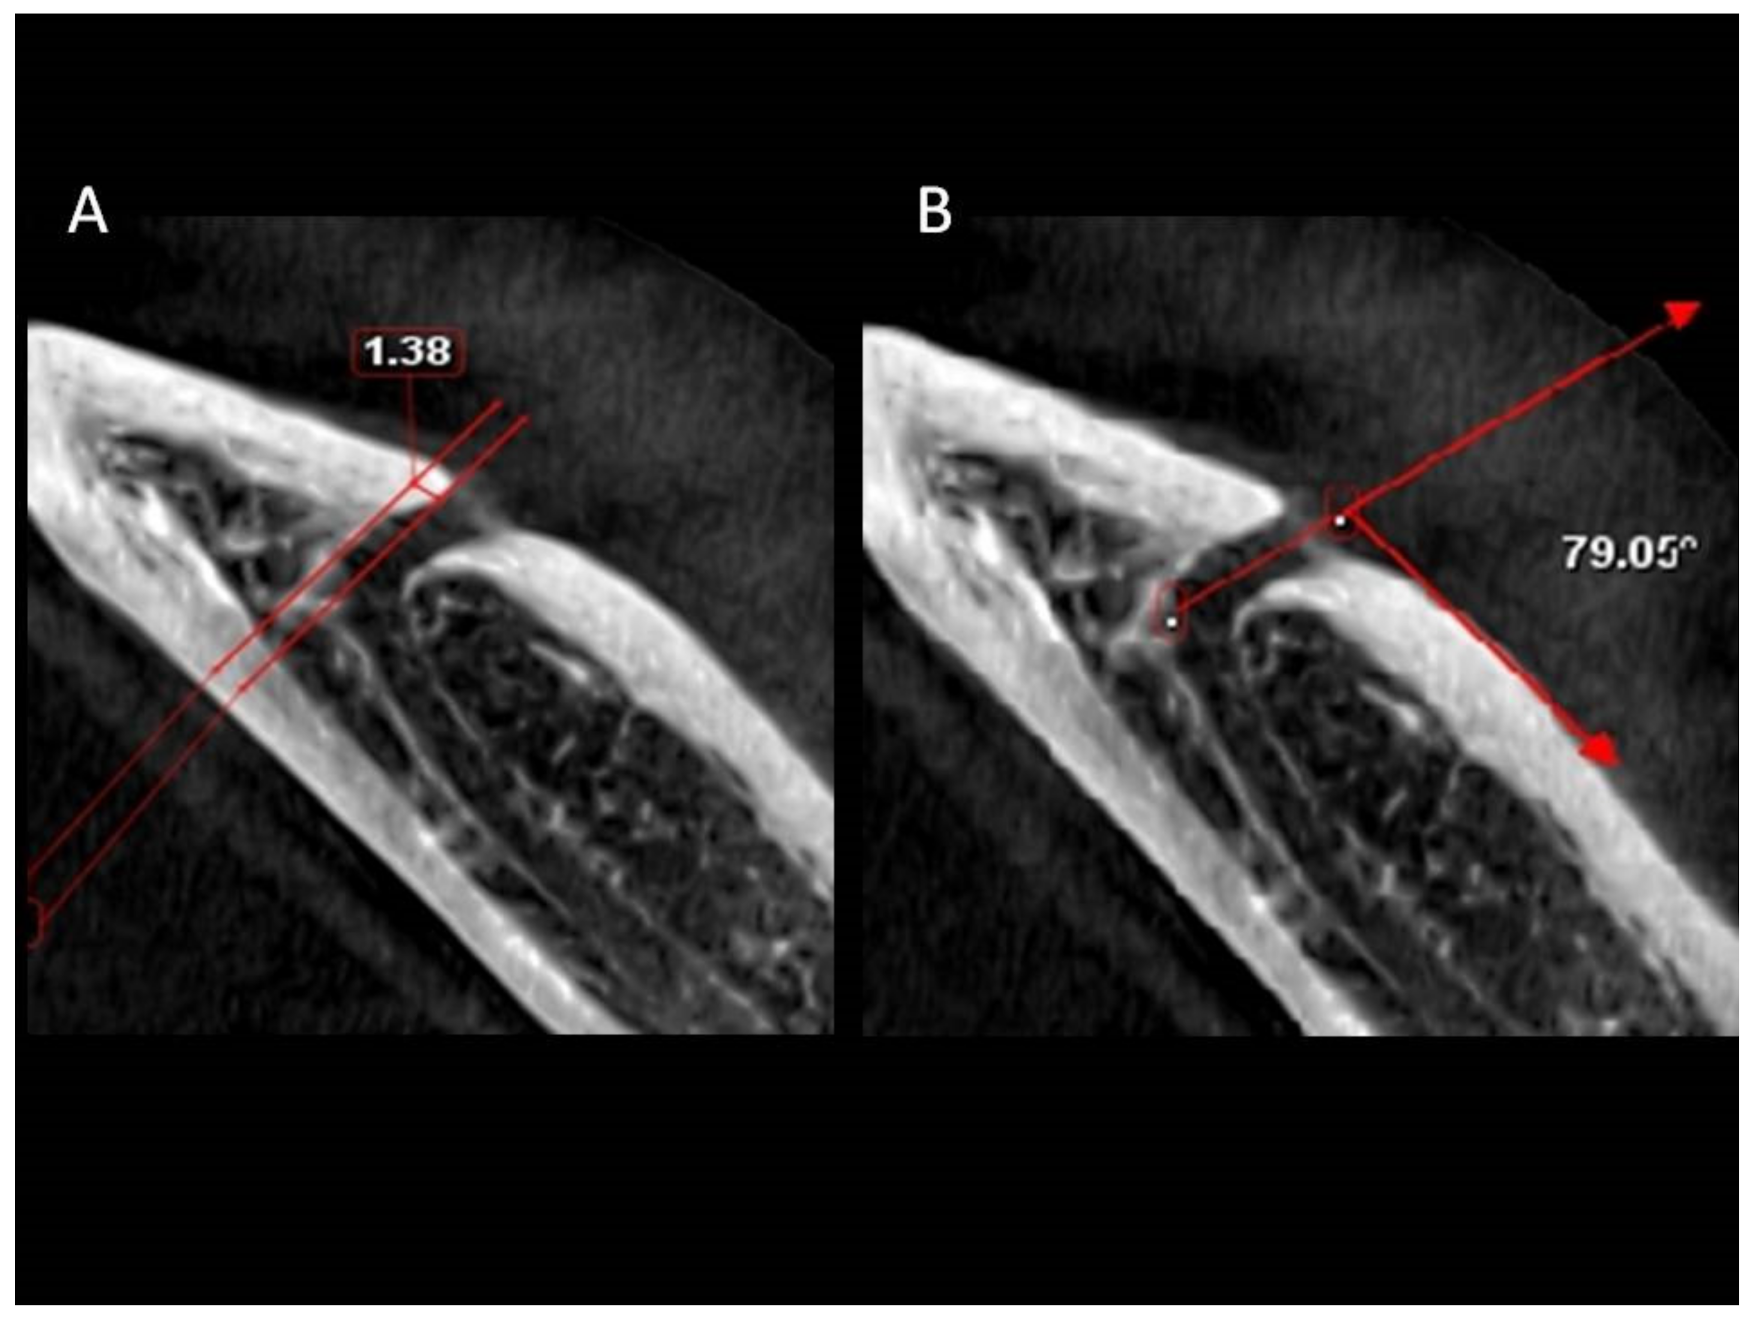

| Axial view | ||||||||||

| Angulations of MeC in axial view | 39.63 | 127.76 | 76.40 | 16.64 | 30.79 | 128.18 | 77.65 | 17.67 | 0.631 | 0.528 |

| Mesial extension of AL | 0.00 | 7.03 | 1.28 | 1.19 | 0.00 | 4.98 | 1.09 | 1.08 | 1.462 | 0.145 |